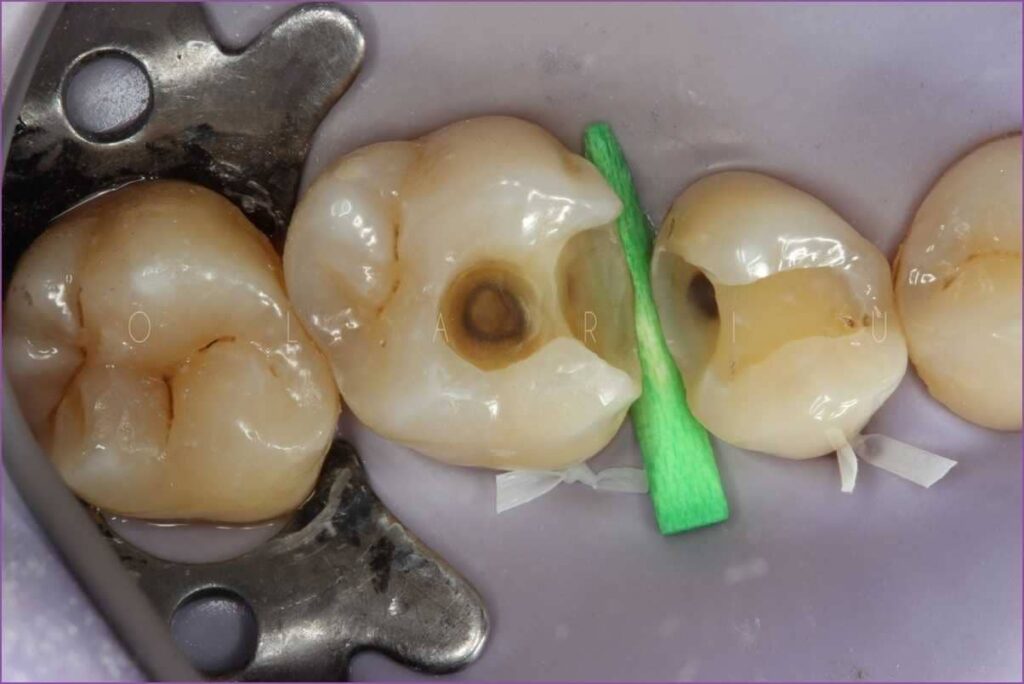

A fenti képen jól megfigyelhető a foganyag hiánya. (Természetesen már a kezeléshez előkészített fogat láthat, amelyekből eltávolítottak minden károsodott foganyagot.)

- A szakszerű ellátás során a lyukas (szuvas) fogból eltávolítunk minden, a szuvasodás által érintett foganyagot, hogy ezáltal a bajt okozó baktériumoktól is megszabadítsák a fogat.

- A kialakult üreget speciális anyagokkal készítjük elő (alábélelők, ragasztóanyagok).

- Erre jön a tömőanyag (vagy a fog nagyobb hiánya esetén az inlay).

Az inlay, más szóval betét, tulajdonképpen a fogtechnikus által készített, ragasztott tömés. Akkor kerül sor az alkalmazására, amikor például a szuvasodás nagyon kiterjedt, a fog több felszínét is érinti, vagy a szuvasodás kiterjed több fogra is. A betét hatalmas előnye, hogy a fog épen maradt része megmenthető, a fogat nem kell kihúzni. A betétet a fog hiányzó részének alakjára készítik – ez a fázis egy fogtechnikai laborban zajlik -, és így kipótoljuk a fognak a szuvasodás miatt elvesztett részét.